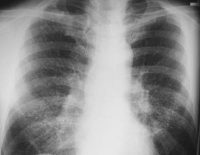

Учитывая преимущественно микронные и субикронные размеры взвешенных в атмосфере частиц, их форму и химический состав, исследования и рекомендации ВОЗ по содержанию в воздухе твердых частиц размерами менее 10 и 2,5 мкм, результаты медико-экологических исследований из литературных источников, эксперт пришел к выводу о существенном (недопустимого) риска для населения обследованной территории заболевания дыхательных путей (фиброз, гранулема, силикоз легких), в том числе онкологических, вследствие пылевого загрязнения атмосферы, вызванного хозяйственной деятельностью Трипольской ТЭС